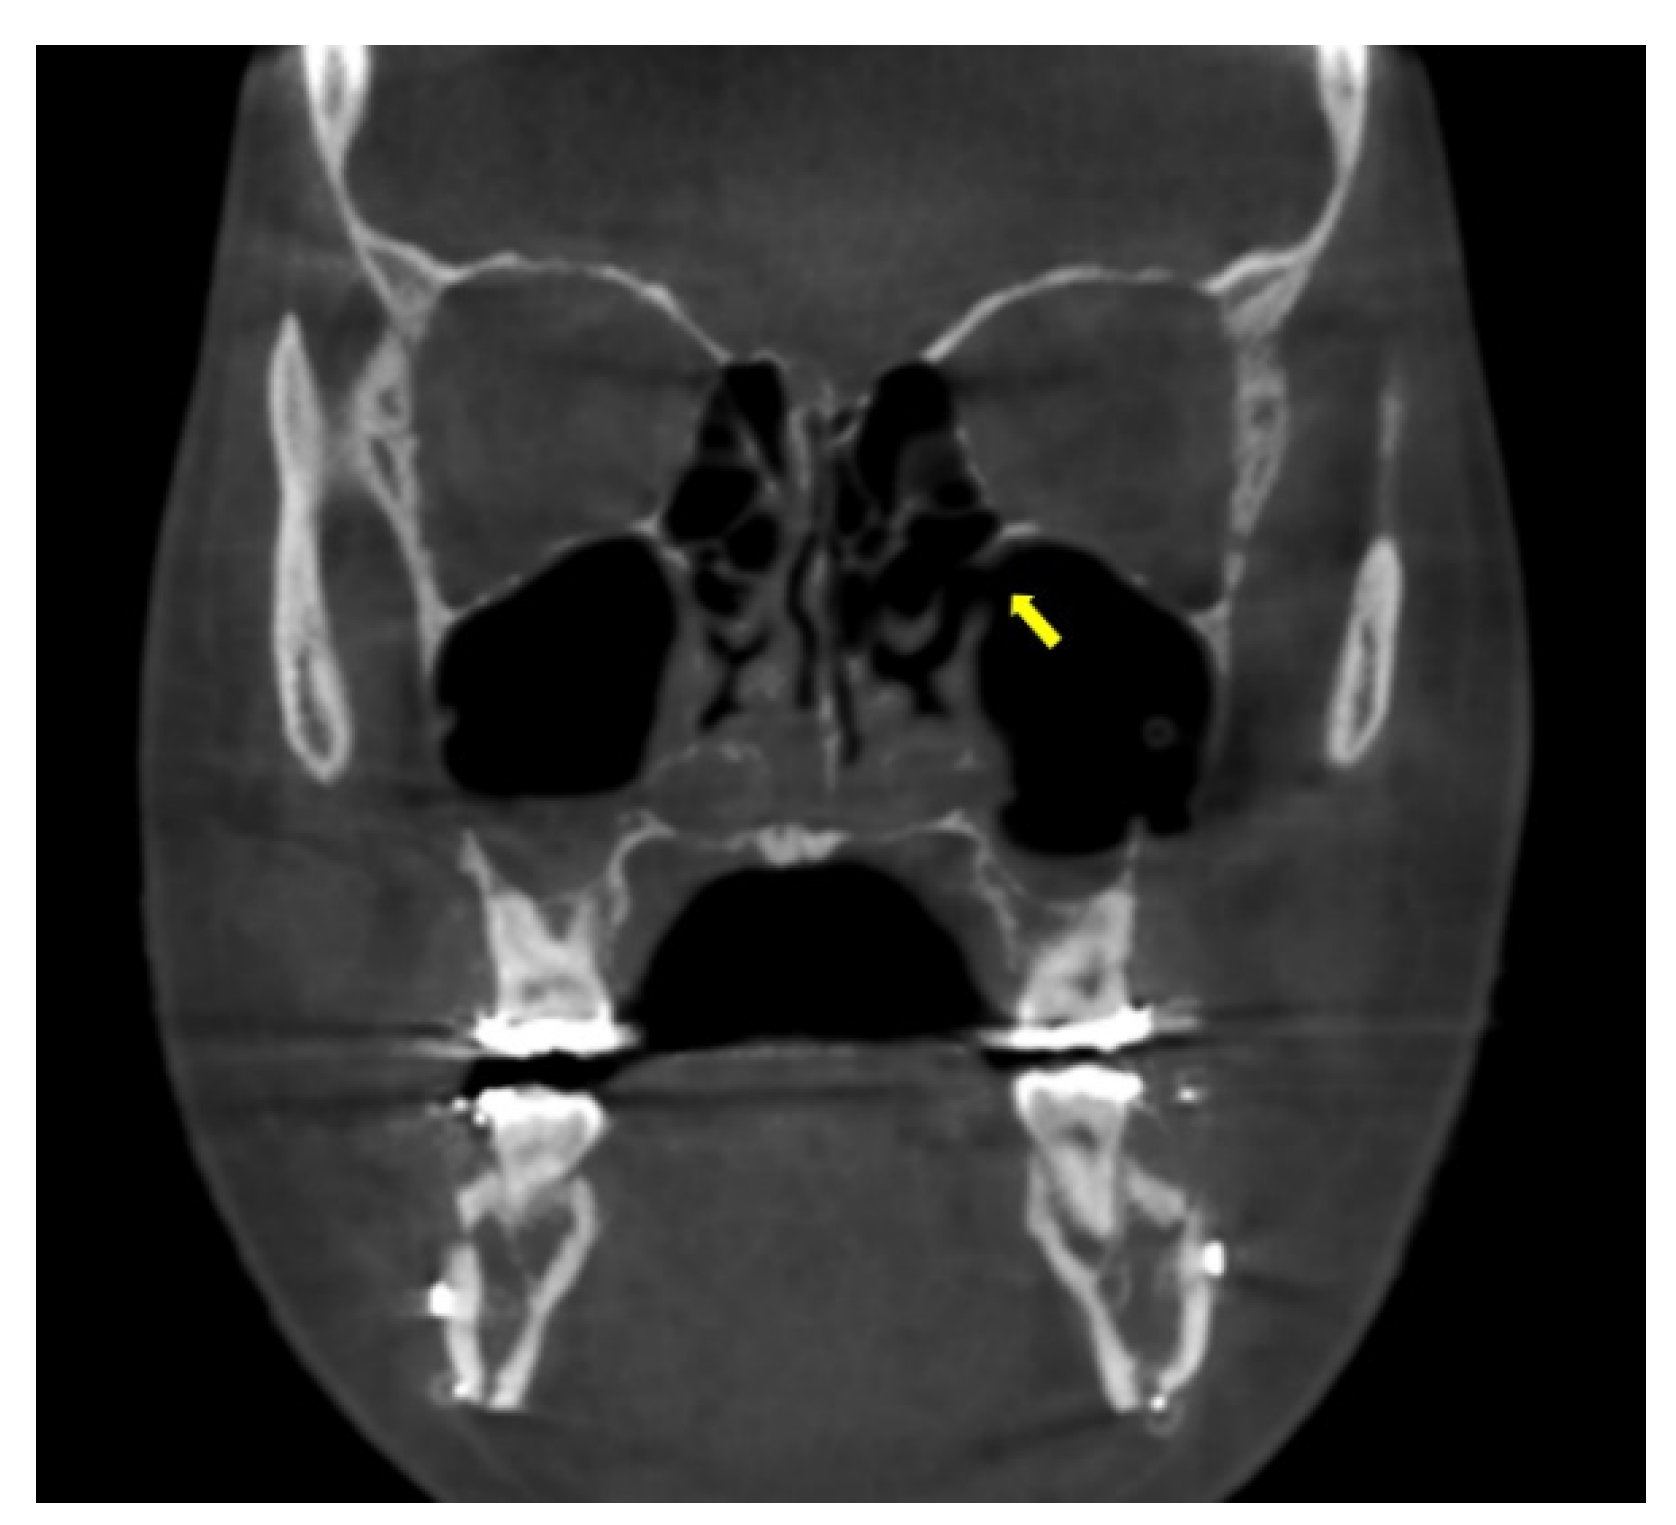

2.2. Radiological Analysis

3. Results